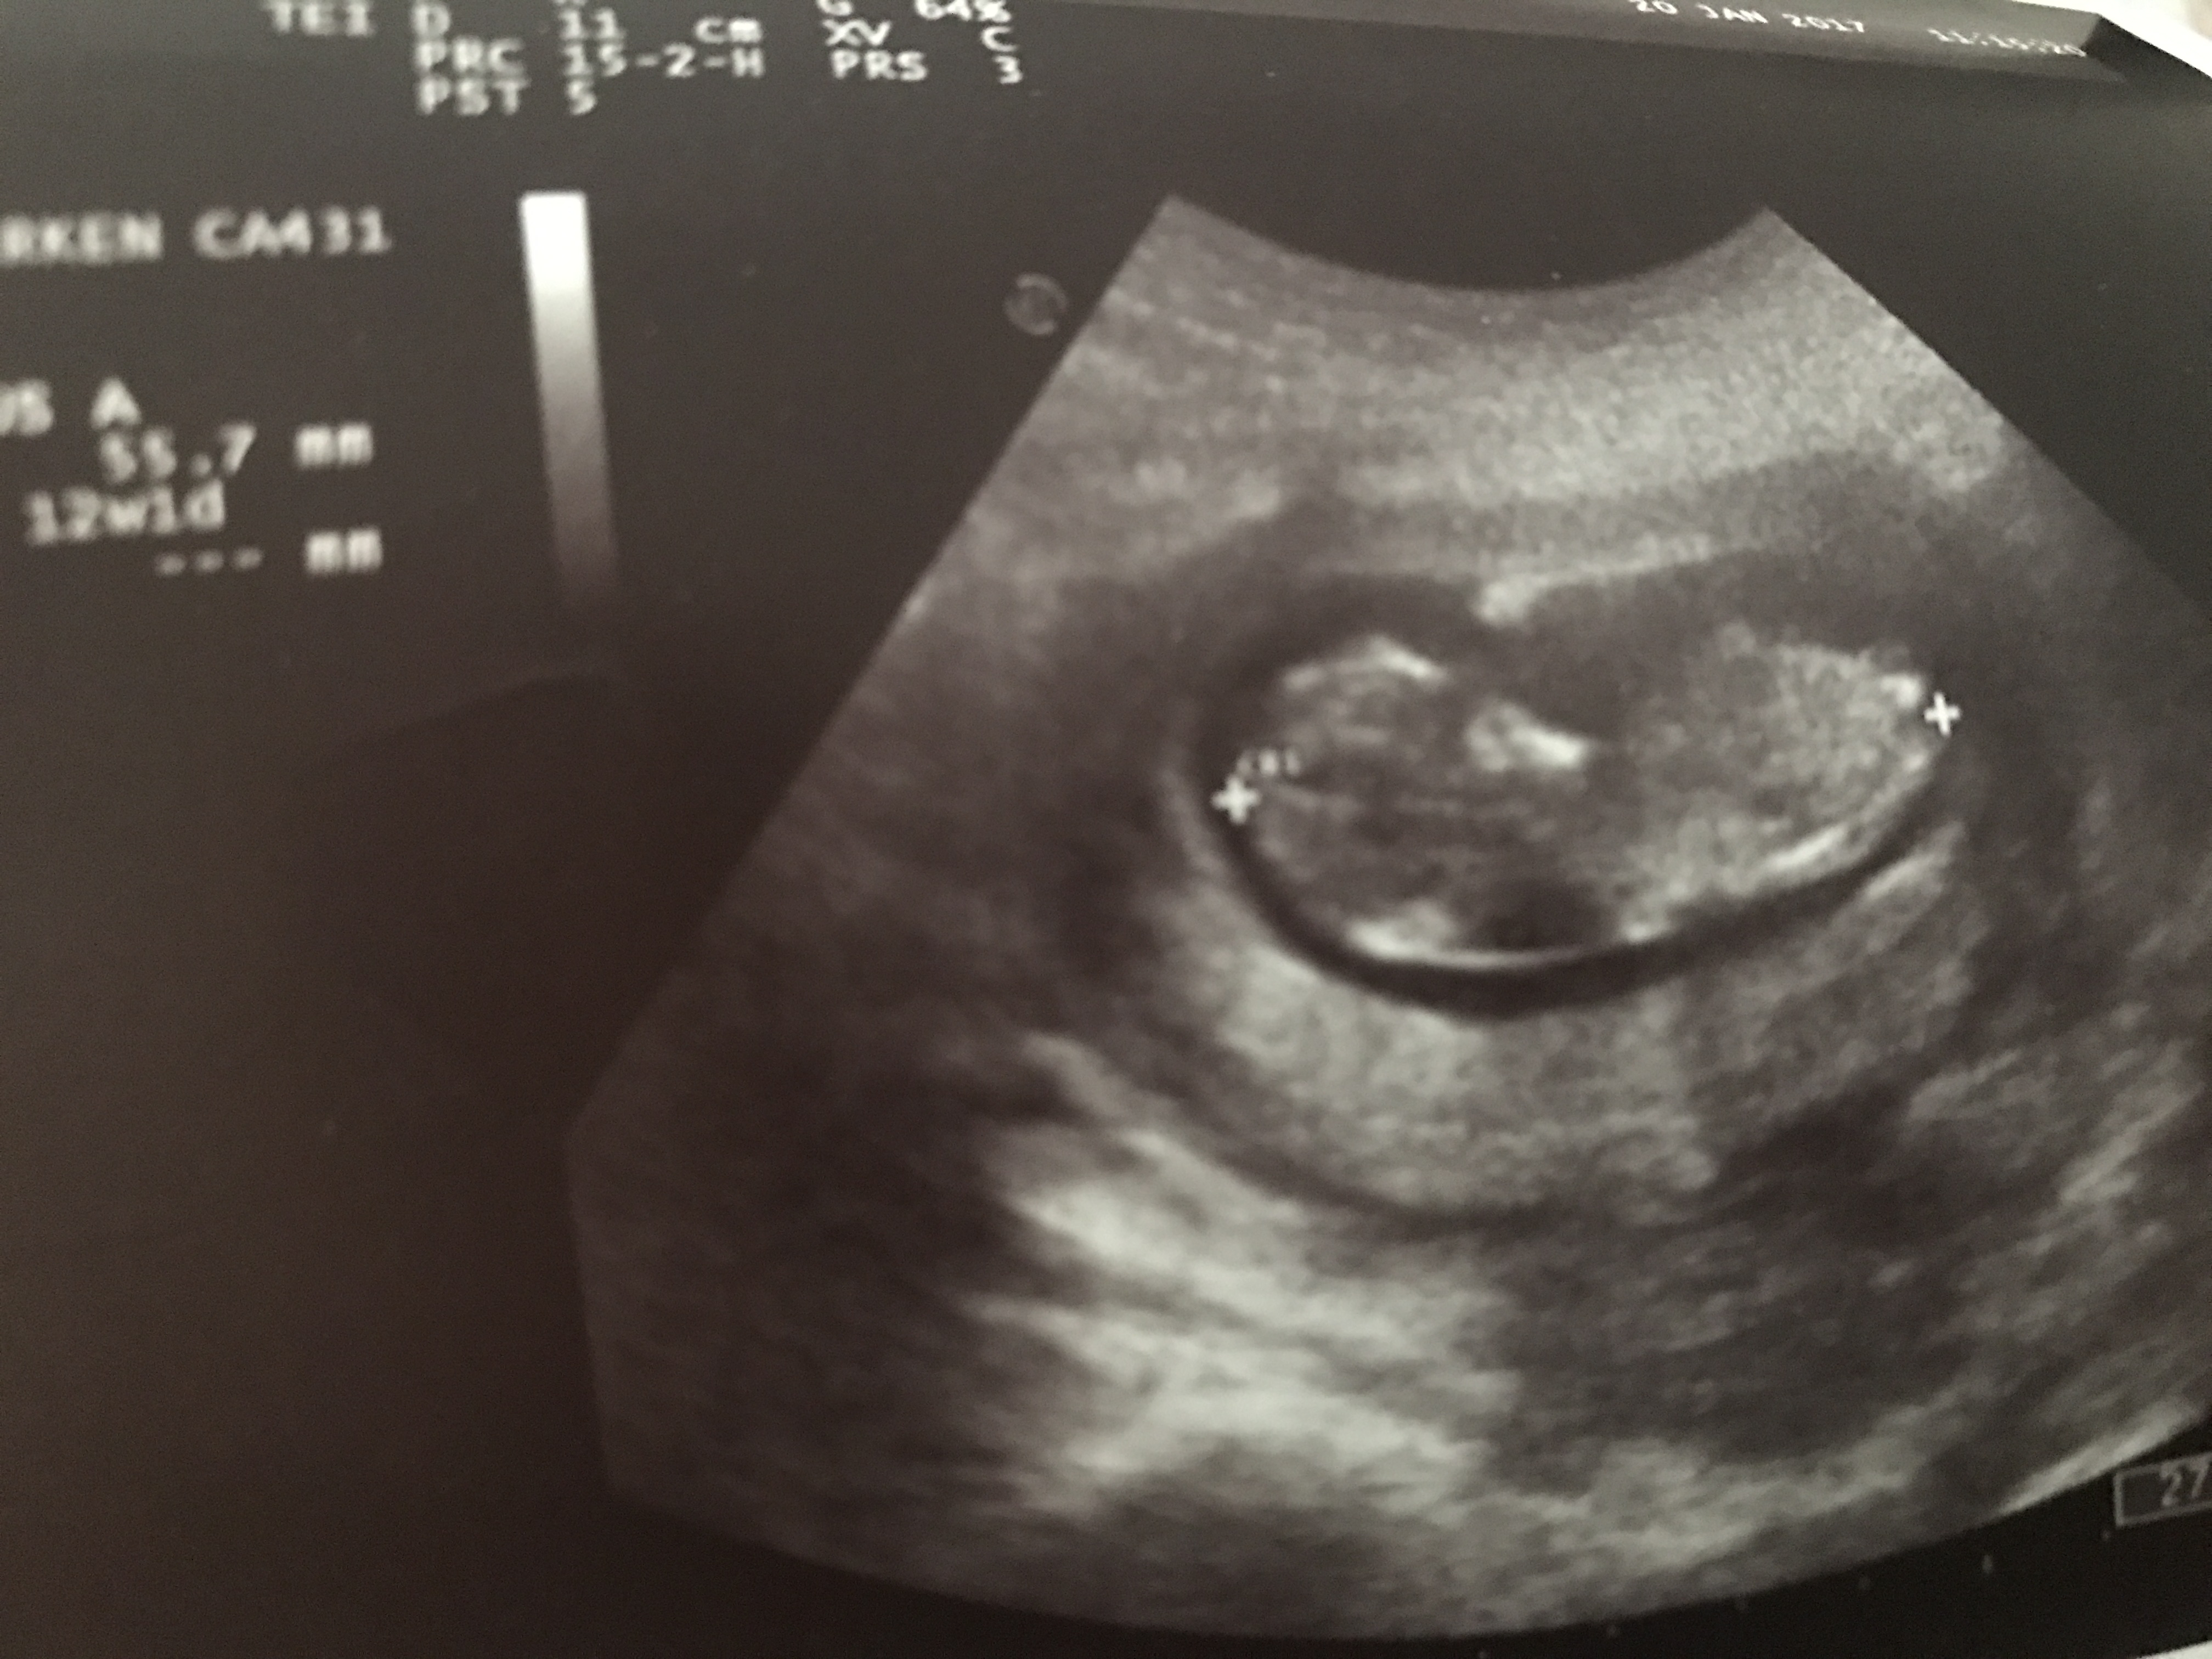

Aysem44 Yeni Üye Üye 1 Mart 2017 #200 Merhaba benim bebeğim içinde yorum yapabilirmisiniz Ekli dosyalar 20170301_114312.jpg 3,6 MB · Görüntüleme: 569